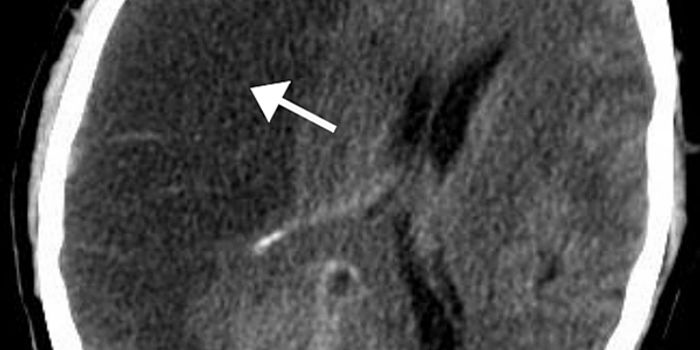

MAY 04, 2016NeuroscienceRupture of small blood vessels in the brain can cause hemorrhagic stroke and brain microbleeds, and finding the fastest ...